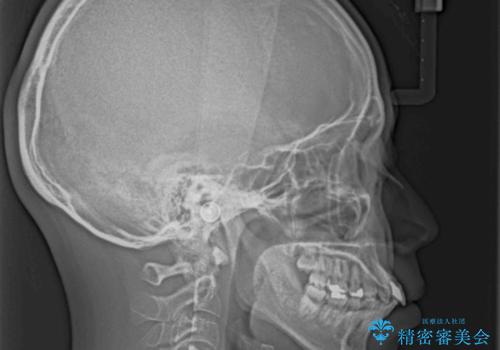

- 飛び出した前歯を気にして来院された患者様です。

口元を引っ込めるために上下左右の第一小臼歯4本を抜歯することとしました。